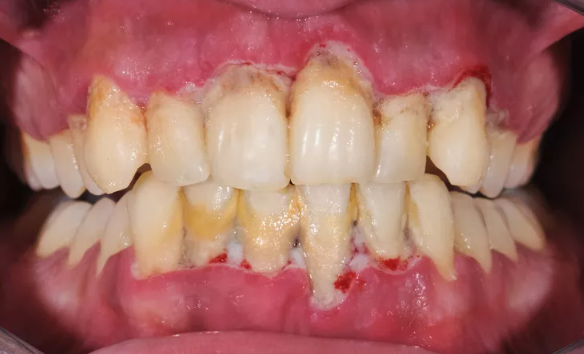

사진이 좀.. 부담스러우실 수 있으니 각오를 하고 보셔야 합니다...! (전 사실 별 감흥이 없습니다만..)

이런 사진 정말 죄송하지만 (그래서 일전에 경고를..! ㅠㅠ) 정말 치석이 어디까지 있을지 예측도 안되는 분들도 있습니다.

전체적으로 이럴수도 있고, 어금니만 이럴수도 있고....

그런 분들은 수술적 잇몸치료를 시행하여야만, 구석구석 꼼꼼히 잇몸치료를 해드릴 수 있어요.